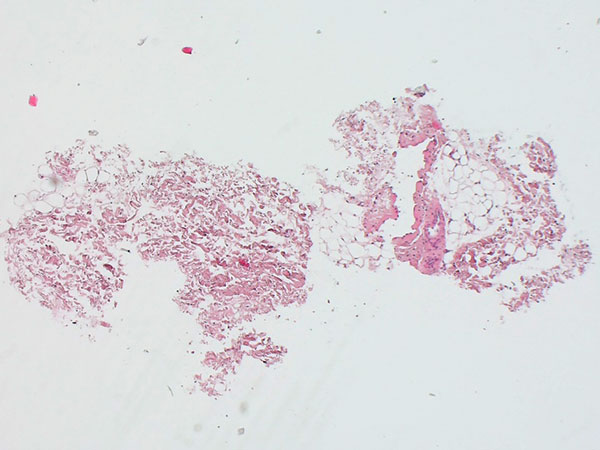

Histopathologisches Bild, Hämatoxylin-Eosin-Färbung (HE), hier 25-fache Übersichtsvergrößerung: Es findet sich ein fuchsbauartiger, dysplastischer, venenartiger Gefäßhohlraum. Dieser ist eingebettet in soweit normales Fettgewebe und Stroma.

Histopathologisches Bild, Hämatoxylin-Eosin-Färbung (HE), hier in 200-facher Vergrößerung: Es zeigt sich ein mit Endothel ausgekleideter „leerer Raum“ mit einzelnen, zentral enthaltenen Erythrozyten sowie einer fehlgebildeten, dünnen venösen Gefäßwand. Der „leere Raum“ ist außen von Gefäßendothelzellen berandet. Daneben sichtbar eine ganz normal aufgebaute Arteriole, diese ist nicht pathologisch.